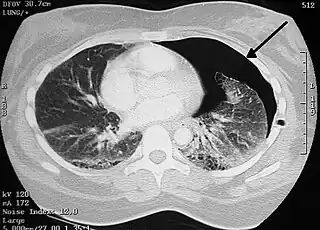

Tomografía axial computarizada

Aunque el TAC supone el gold standard en la detección de neumotórax, superando en sensibilidad y especificidad a la radiografía,[41] generalmente este no se necesita para establecer el diagnóstico de neumotórax, pero puede resultar de utilidad en situaciones particulares. En algunas patologías de las vías respiratorias, y especialmente en presencia de enfisema, es posible que ciertas estructuras pulmonares (como las cavitaciones) tengan la misma apariencia que un neumotórax en la radiografía, en cuyo caso el tratamiento específico de neumotórax no está indicado.[20] En ciertos casos de traumatismo el paciente es incapaz de permanecer en posición vertical durante la realización de la radiografía, lo cual dificulta la identificación del neumotórax en la imagen. Para estas situaciones, el TAC puede indicarse al poseer una mayor fiabilidad.[29]

Otro uso del TAC es para la identificación de lesiones concomitantes, ayudando a detectar bullas o lesiones quísticas en casos de neumotórax primario, y como herramienta de búsqueda de la causa de origen en el neumotórax secundario.[20][31]